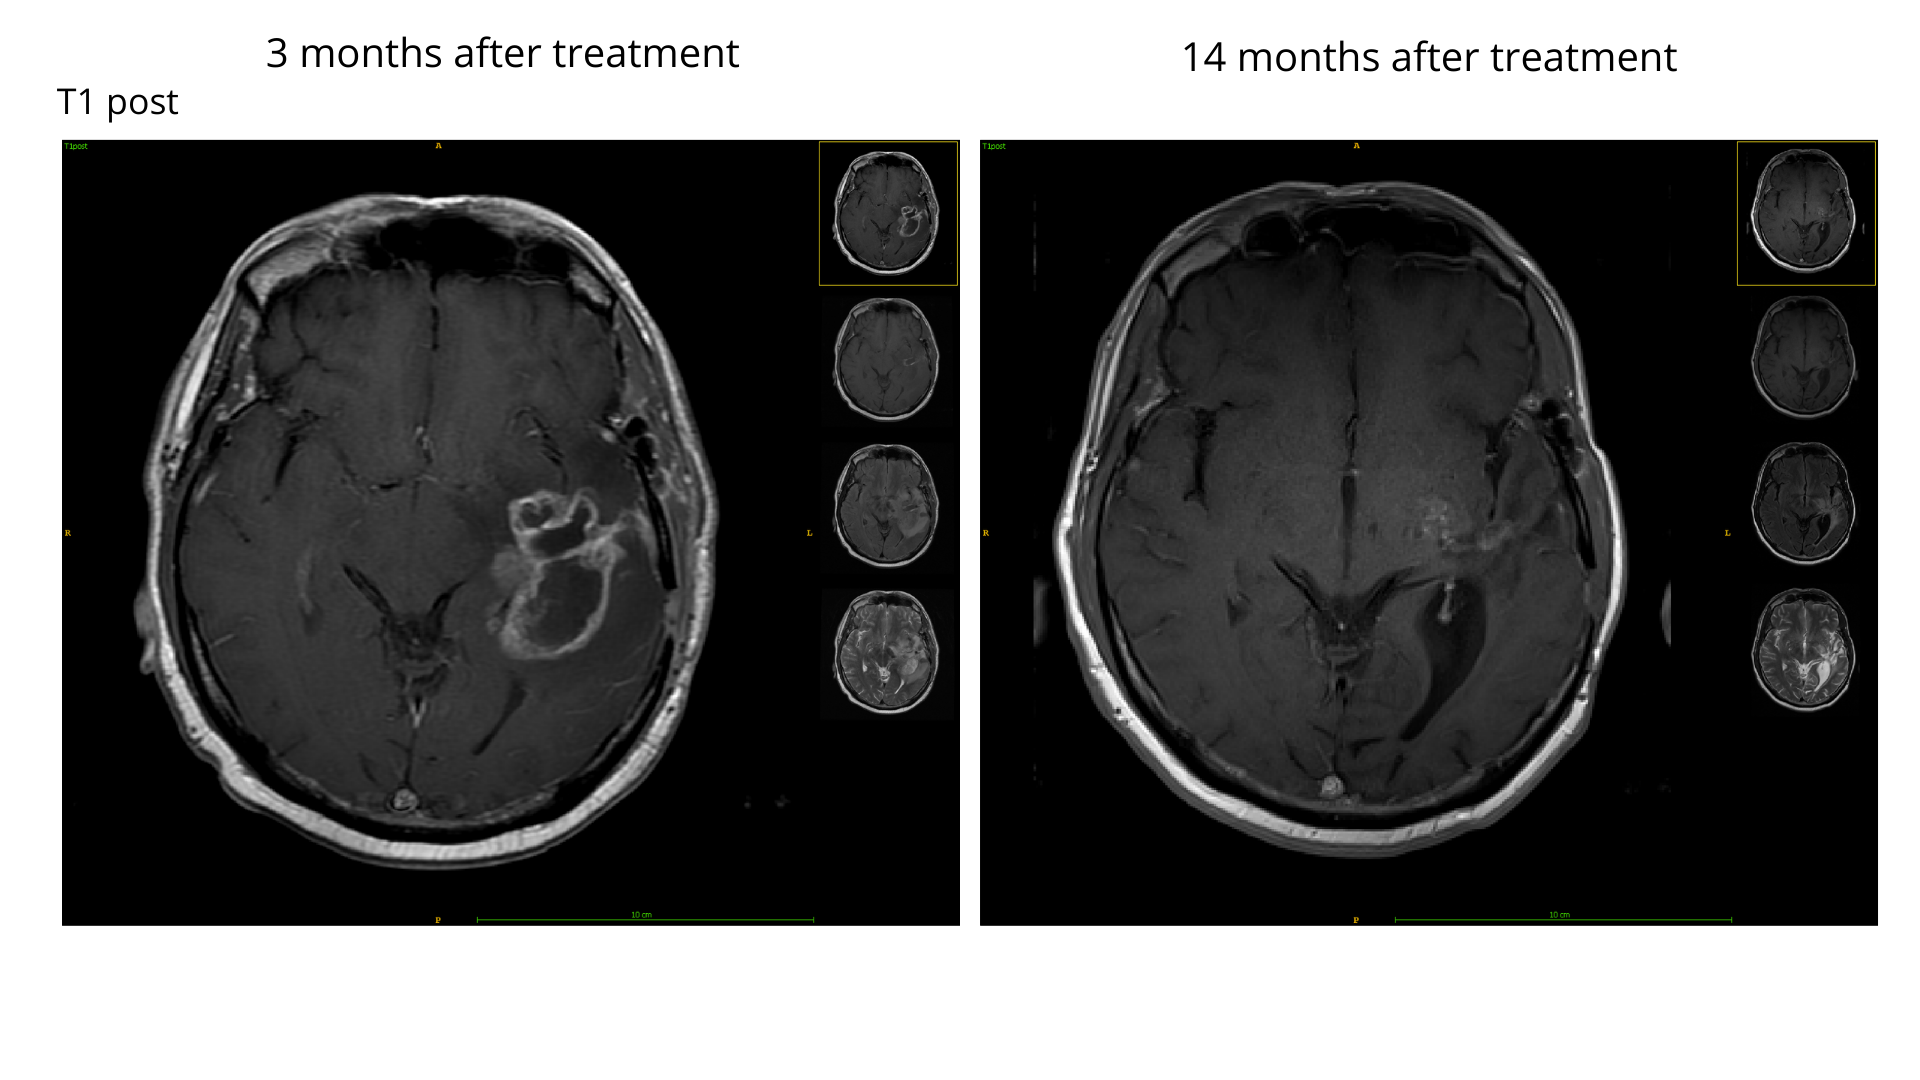

Visualization: Brain tumor segmentation: regression

The patient responded well to the treatment, and we observed a strong enhancing tumor (ET) regression for this patient a year after the treatment. Automatic RANO measurement (marked with blue line segments in both scans) and ET volume both significantly decreased (-78% and -93% respectively). In summary, the region of edema became much smaller, and necrosis was nearly absent.

Edema: 97 cm3

Enhancing (ET): 28 cm3

Necrosis: 19 cm3

Tumor regression

RANO -78%

ET volume -93%

Edema: 39 cm

Enhancing (ET): 2 cm3

Necrosis: 1 cm3